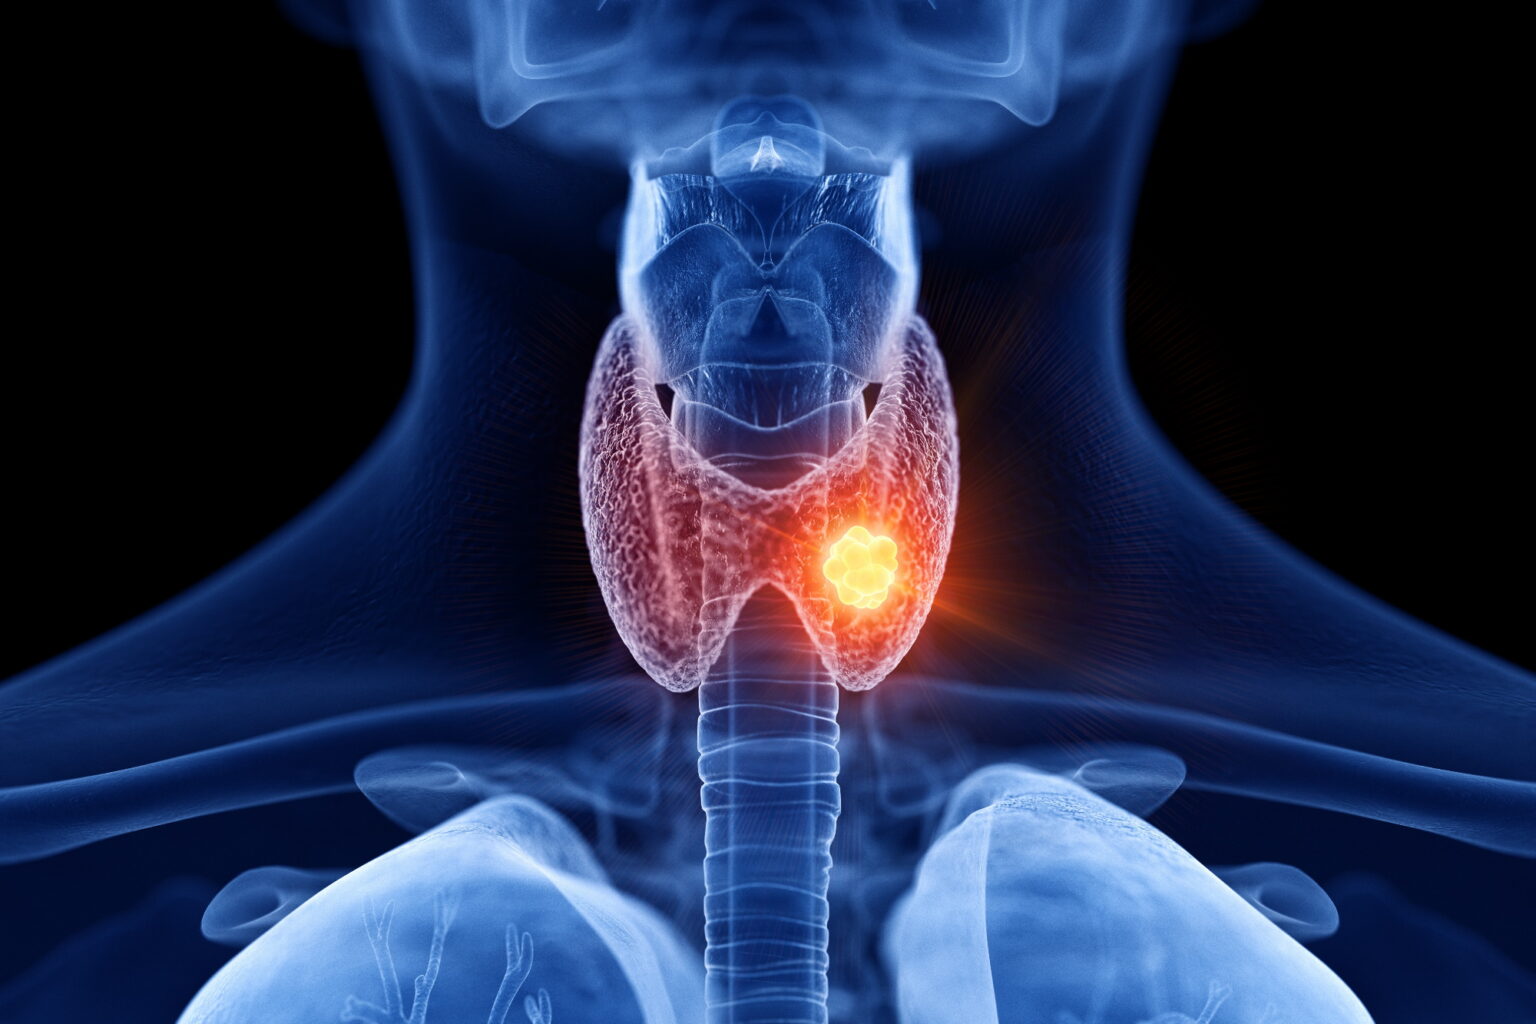

Ο καρκίνος του θυρεοειδούς είναι καρκίνος που εντοπίζεται στον θυρεοειδή αδένα, τον μικρό αδένα που βρίσκεται στο μπροστινό μέρος της βάσης του λαιμού.

Παράγει και απελευθερώνει ορμόνες οι οποίες βοηθούν στη ρύθμιση του μεταβολισμού.